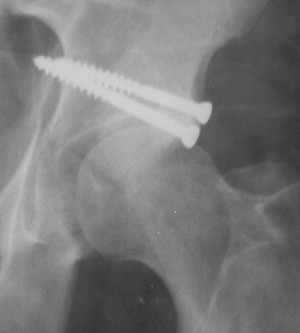

Re: Перелом acetabulum и проксимального отдела бед

Привет! Вот недавно прооперировали похожий на ваш случай - впадина + шейка (правда у нас впадина поперечный+задний край). После травмы прошло 4 недели. мужчине 46 лет. С такой комбинацией все показания к первичному протезированию. Морально и технически мы к этому уже созрели.Но больной не собрал денег на протез. Выполнили остеосинтез впадины и шейки, прекрасно понимая, что головка вскоре рассосется, мы хотя бы надемся что к этому времени таз срастется, как говорится создали все условия для дальнейшего протезирования (может, и протез в последующем подешевле будет, в смысле, без укрепляющего кольца?). Привет Рункову!

Отправитель: Рунков 27 Сентябрь 2005, 09:57

Привет Алекей! Сделано неплохо, поздравляю, хотя второй винтик можно было бы и подлиннее в шейку загнать! Пара вопроов: доступ такой же? головка была свободной или висела на капсуле?

Отправитель: Алексей Смирнов 27 Сентябрь 2005, 22:35

Согласен, можно было и подлиннее. Доступ такой же - чрезвертельный, только разрез кожи прямой (а не Y, чего то я разницы не ощущаю). Головка была абсолютно свободной (то есть во время остеосинтеза таза лежала в стакане и не мешалась). Шансов, что она прирастет 0,00001%. Хотели даже выбросить, но привинтили как временный биологический протез (читай свободный трансплантат), чтоб на период срастания таза бедро проксимально не ушло (может ортопеды потом спасибо скажут). Ну а у вас первичное протезирование при переломе впадины тоже пока полько в планах?